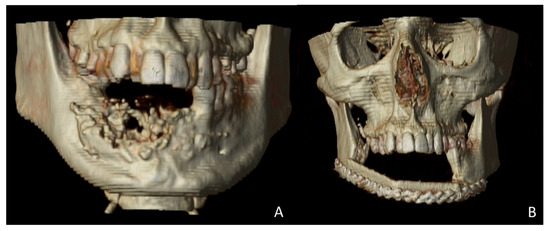

A 38-year-old patient was referred to our Department reporting progressive deformity of the mandibular symphysis with loss of teeth. Panoramic radiography and 3D CT scan showed a lytic lesion with destruction of the external mandibular cortex (Figure 1A).

The patient was diagnosed with a mandibular ameloblastoma, affecting the mandibular symphysis and both mandibular bodies. Tumor resection with segmental mandibulectomy and clear margins, and immediate reconstruction with a two-segment fibula flap was performed (Figure 1B). Six months later, a vertical discrepancy between the remnant mandible and the fibula flap was assessed and a virtual surgical planning (VSP) with a cortico-cancellous iliac crest graft was planned. VSP was performed with the biomedical engineer (Maffinter®, Madrid, Spain) and a three-dimensional virtual reconstruction of the defect was performed with two titanium CAD/CAM meshes (Figure 2) with 1.5 mm diameter pores.

Figure 1. Postoperative 3D scan. (A) CT Scan showing destruction of the mandibular symphysis due to ameloblastoma. (B) CT Scan with segmental mandibulectomy from left mandibular body to right mandibular angle and immediate reconstruction with fibula free flap.